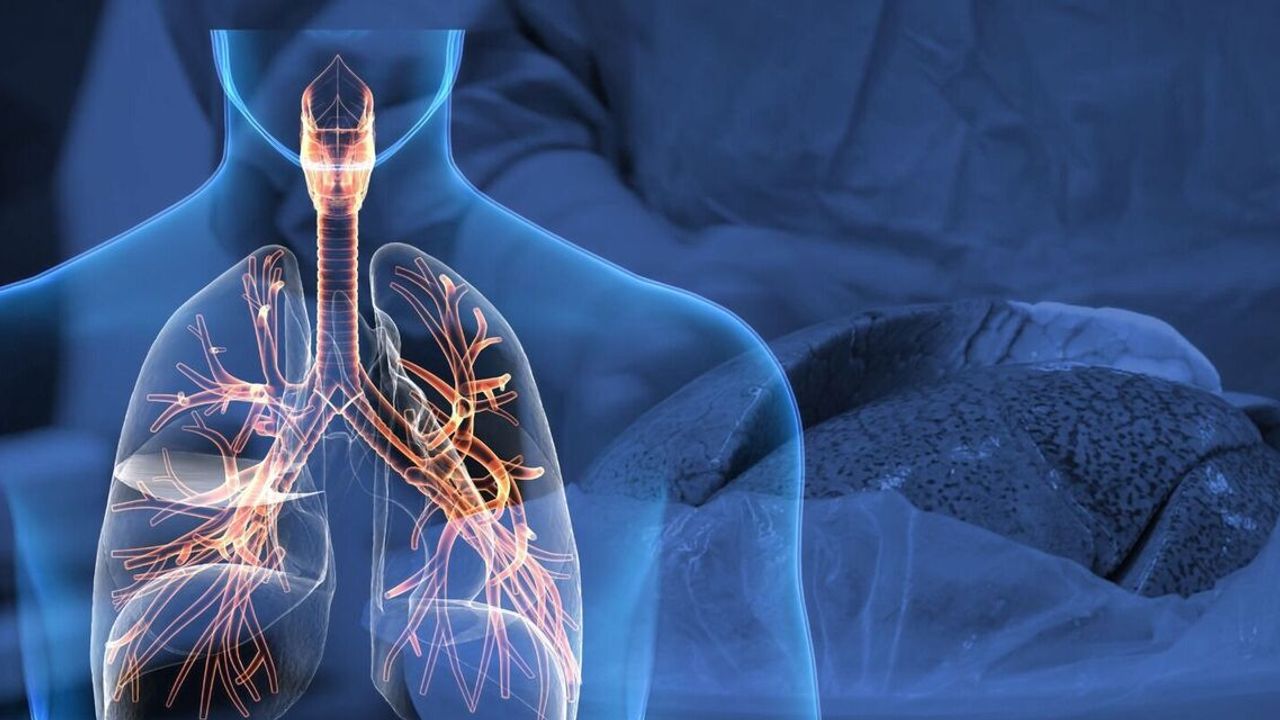

Cilt, meme, akciğer, prostat, mide, kalın bağırsak (kolon), rahim ağzı (serviks) kanseri ve lenf bezi tümörleri, "habis tümör" veya "ur" olarak da adlandırılan hastalığın en yaygın türleri arasında yer alıyor.

Dünya genelinde 2022'de akciğer, meme ve kolorektal en sık görülen kanser türleri oldu. Akciğer kanseri, 2,5 milyon yeni vaka ile toplam yeni vakaların yüzde 12,4'ünü oluşturdu ve küresel olarak en sık görülen kanser türü olarak kayıtlara geçti.

EN FAZLA ÖLÜM AKCİĞER KANSERİNDEN

Aynı yıl en fazla ölüm 1,8 milyon ile akciğer kanseri nedeniyle yaşanırken, bu rakam kanserden yaşanan can kayıplarının yüzde 18,7'sine karşılık geldi. Kolorektal kanser nedeniyle 900 bin kişi yaşamını yitirirken, bunu 760 bin ile karaciğer kanseri, 670 bin ile meme kanseri ve 660 bin ile mide kanseri takip etti.

En sık görülen ve ölümcül olan kanser türü, kadınlarda meme kanseri, erkeklerde ise akciğer kanseri oldu.

Türkiye'de erkeklerde 132 bin 476 ve kadınlarda 107 bin 537 kanser vakası tespit edilirken, akciğer, meme ve kolorektal en fazla görülen kanser türü oldu.